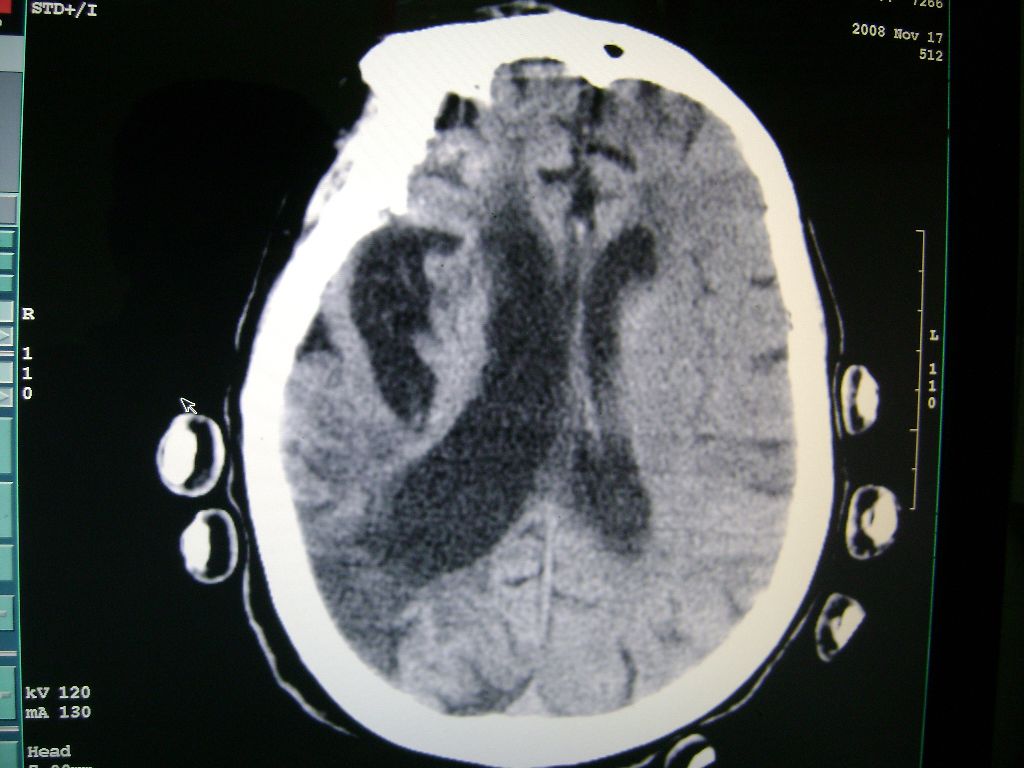

右侧额颞枕顶叶脑软化灶,脑萎缩,大脑中动脉壁钙化。

右脑软化灶,考虑再次梗塞,高密度灶出血?钙化?。。。量ct值,改窗宽,位

右侧半球陈旧性卒中,不除外伴有新病灶,左额叶梗塞,双侧大脑中动脉钙斑

右侧额颞枕顶叶脑软化灶,脑萎缩,大脑中动脉壁钙化。不支持出血(密度高,边界清且局限)顶枕区似有新发梗塞,建议核磁

1)右侧额颞枕顶叶脑软化灶;其内高密度影,多为钙化灶。2)脑萎缩。3)大脑中动脉钙化。

再次脑梗死,右侧额颞枕顶叶脑软化灶,高密度考虑钙化

右侧陈旧脑梗塞伴脑萎缩。脑内点状钙化。大脑中动脉壁钙化灶。无出血灶。

1)右侧额颞枕顶叶脑软化灶并钙化灶可能。2)脑萎缩。3)大脑中动脉钙化。 -